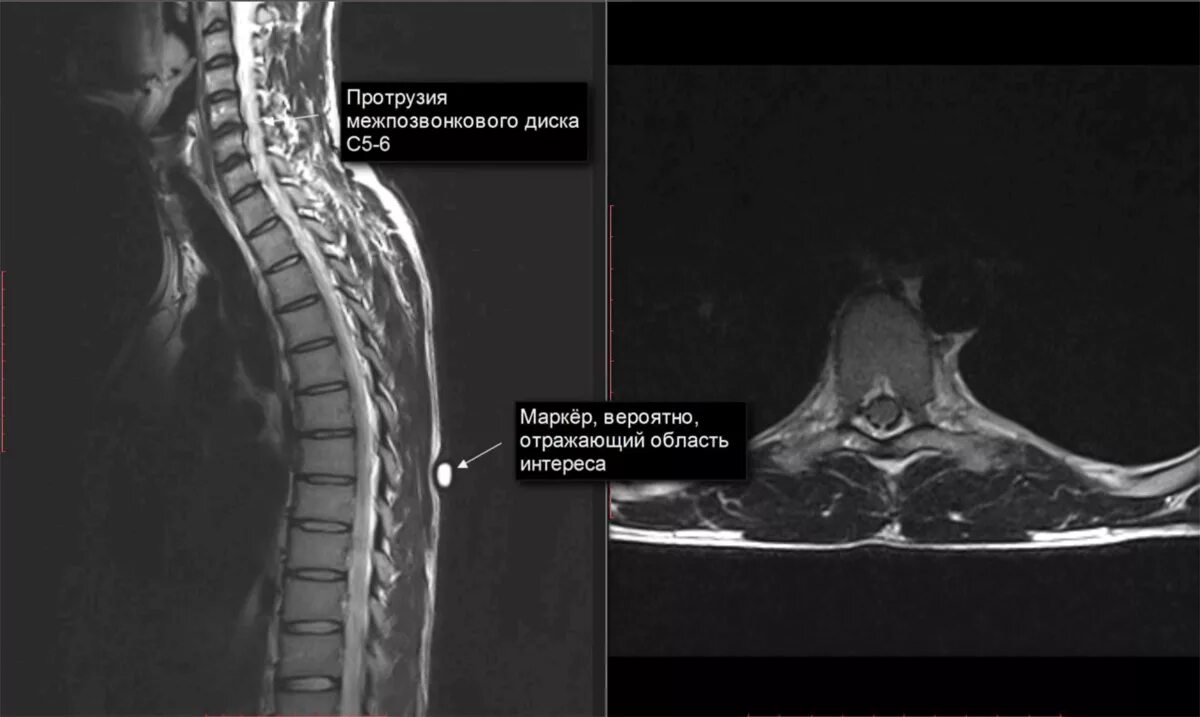

Протрузии грыжи диска шейного